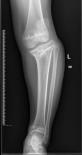

儿童陈旧性孟氏骨折

术前前臂侧位片

术后肘关节侧位片

术后1个月肘关节侧位片

儿童陈旧性孟氏骨折,术前桡骨小头陈旧性脱位,经截骨矫形治疗后1个月,桡骨小头已复位,患儿肘关节屈伸功能(1-2图),前臂旋转功能(3-4图)正常